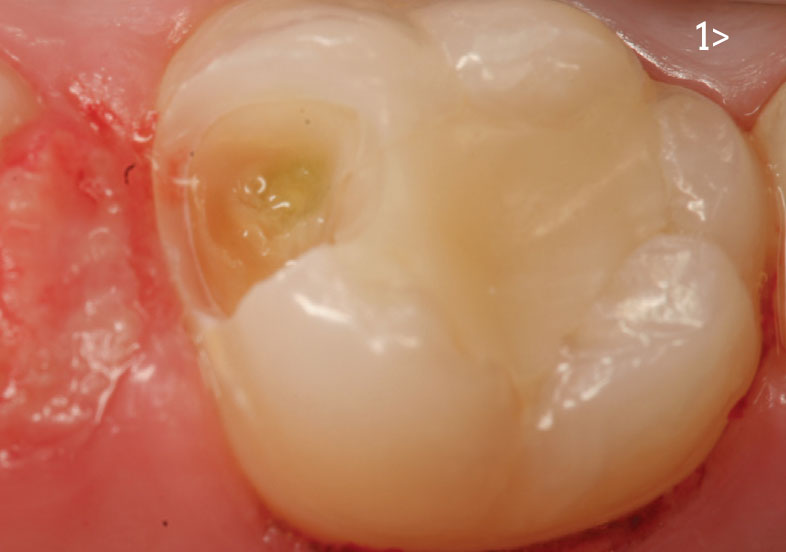

- Fig. 1: Carious pulp exposure appears greenish yellow and possibly purulent.

Endodontic root-canal therapy is indicated.

Case report

A 14-year-old female presented for routine restorative dentistry

on a maxillary molar with no complaints of pain or sensitivity. Radiographic

and clinical examination revealed moderate to advanced

occlusal decay. After anesthetic and rubber dam isolation, the tooth

was accessed with a carbide bur. During caries excavation, the mesial

pulp was exposed resulting in mild hemorrhage (Fig. 5). Upon

examination, this was a carious/mechanical exposure. A cotton pellet

soaked in 2 percent chlorhexidine was held against the exposure until the bleeding stopped. A new soaked cotton pellet was used to

disinfect the rest of the cavity preparation.